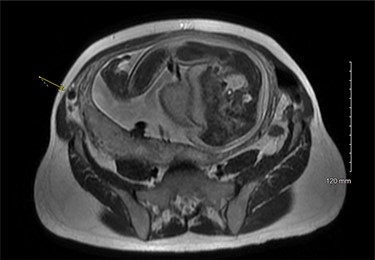

On examination, the patient was a thin woman with a gravid uterus. She was very tender to palpation across the right lateral aspect of her abdomen, extending superiorly from the anterior superior iliac spine. Laboratory data were significant for a leukocytosis with a neutrophilic predominance. An ultrasound was obtained, but the technician was unable to visualize the appendix. The patient continued to have severe pain on the right side and an abdominal magnetic resonance imaging (MRI) was ordered. The attending radiologist reported a dilated appendiceal tip at 1 cm with surrounding inflammatory changes and free fluid, consistent with tip appendicitis (Figs 1 and 2). The cecum was noted to be superior to its normal position, with the right colon folded on itself, coursing down from the hepatic flexure before turning back upwards. The location of the appendix on the MRI correlated with the patient’s location of maximal pain and tenderness.